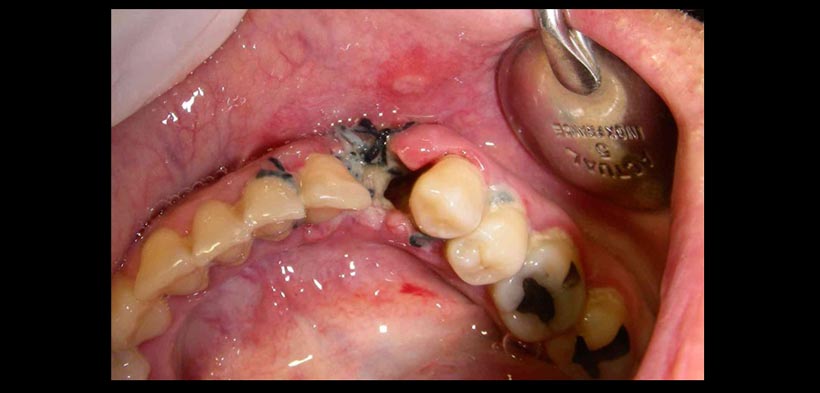

El diagnóstico se realiza por las características clínicas y la sintomatología del paciente, la cual es altamente dolorosa y puede llegar a limitar las funciones en la cavidad bucal. El dolor suele aumentar con la succión o la masticación y persiste durante varios días. Clínicamente se observa el alveolo con una pérdida parcial o total del coágulo sanguíneo. En algunos casos se presenta un coágulo grisáceo que luego se desprende y desaparece completamente. También se percibe mal olor bucal, fetidez a la exploración y edema en la zona.

Fig. 1. Signos clínicos de una alveolitis seca: Alveolo seco, perdida de coagulo sanguíneo, edemo en la zona de extracción, dolor. También se percibe mal olor bucal, fetidez a la exploración.